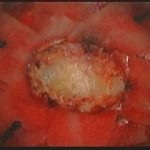

手術前1

摘出 前